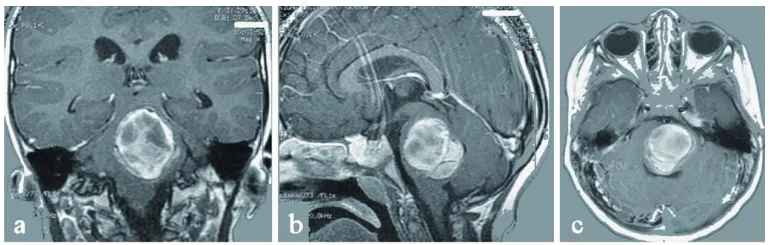

图1 a-c 术前影像:显示患儿桥脑海绵状血管瘤。

复查MRI显示:左侧桥脑存在最大尺寸4×3.5×3cm的巨大海绵状血管瘤(图1 a-c)。

术后患儿神经症状持续改善。术后10天MRI检查证实海绵状血管瘤完全切除,显示先前严重增大的脑干已获减压(图1 d)。患儿出院后接受进一步神经功能康复治疗。

图d 术后:显示海绵状血管瘤完全切除,第四脑室大小恢复,脑干压迫解除。